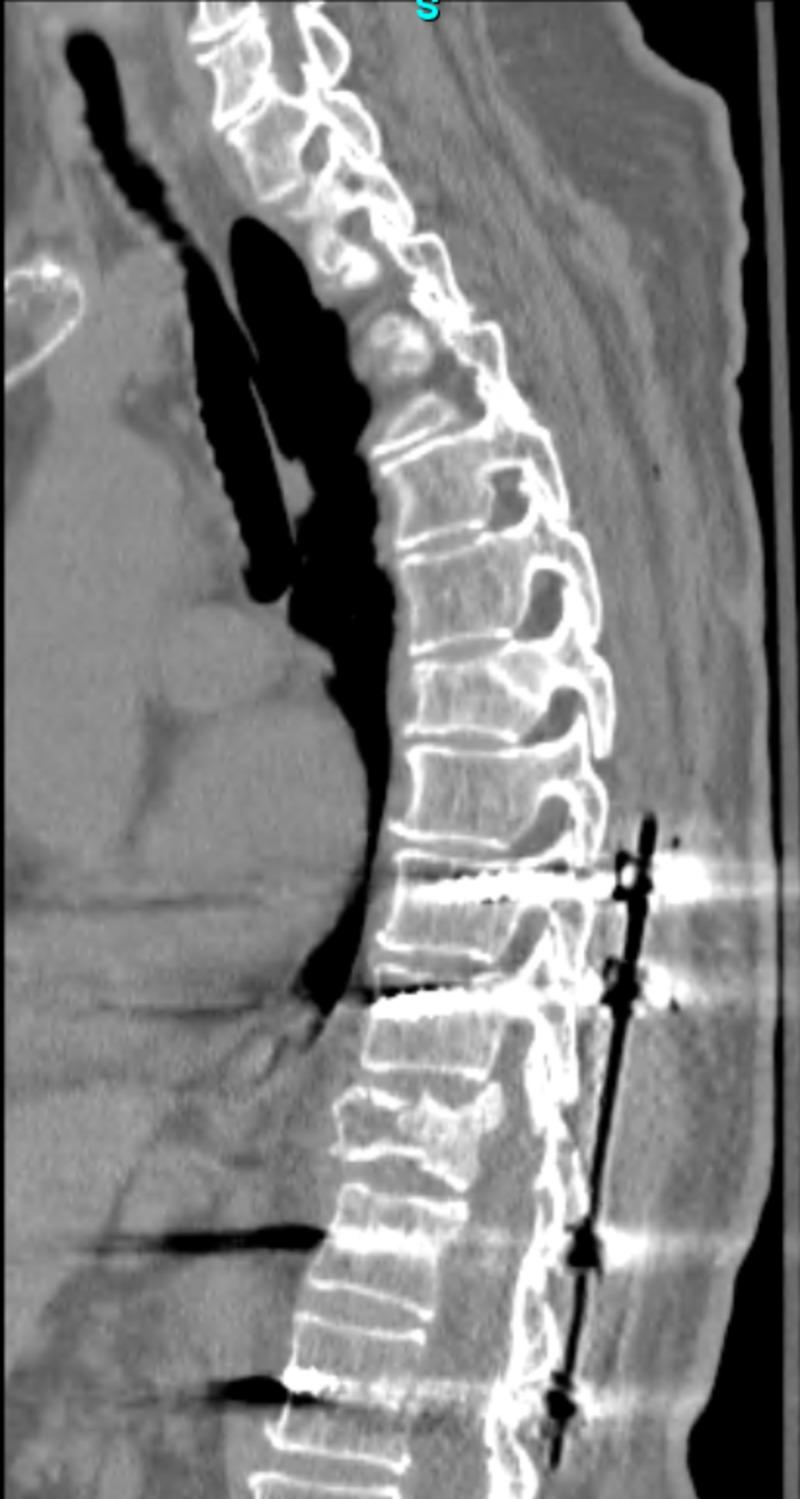

Neurosurgical patients with titanium spinal implant hypersensitivity can be difficult to diagnosis due to its rarity. Suspicion for titanium allergy is generally localized to the hardware site and may initially be thought to be an infectious process. Patients who report anorexia and fatigue over a long duration after the initial post-operative period may be diagnosed with depression rather than a systemic response to spinal metallic instrumentation. To our knowledge, a systemic titanium hypersensitivity reaction to spinal fixation devices has not been reported in the literature. We offer this report to give spine surgeons additional insight into suspected systemic titanium hypersensitivity symptoms which, if remain unidentified, can severely impair patient outcomes. A 67-year-old female with an unreported nickel allergy developed severe debilitating anorexia and fatigue one month post operatively, secondary to minimally invasive thoracic spinal fixation for T11 burst fracture with disruption of posterior elements. Over a two year period, weight loss reached approximately 25 kilograms with loss of muscle mass and subcutaneous tissue surrounding the spinal implants. The screws and rods were removed to avoid skin erosion. Upon hardware removal, the patient had rapid weight gain, improved stamina and generalized sense of well-being. We recommend the removal of spinal hardware in patients with suspected systemic titanium hypersensitivity reaction.

摘要